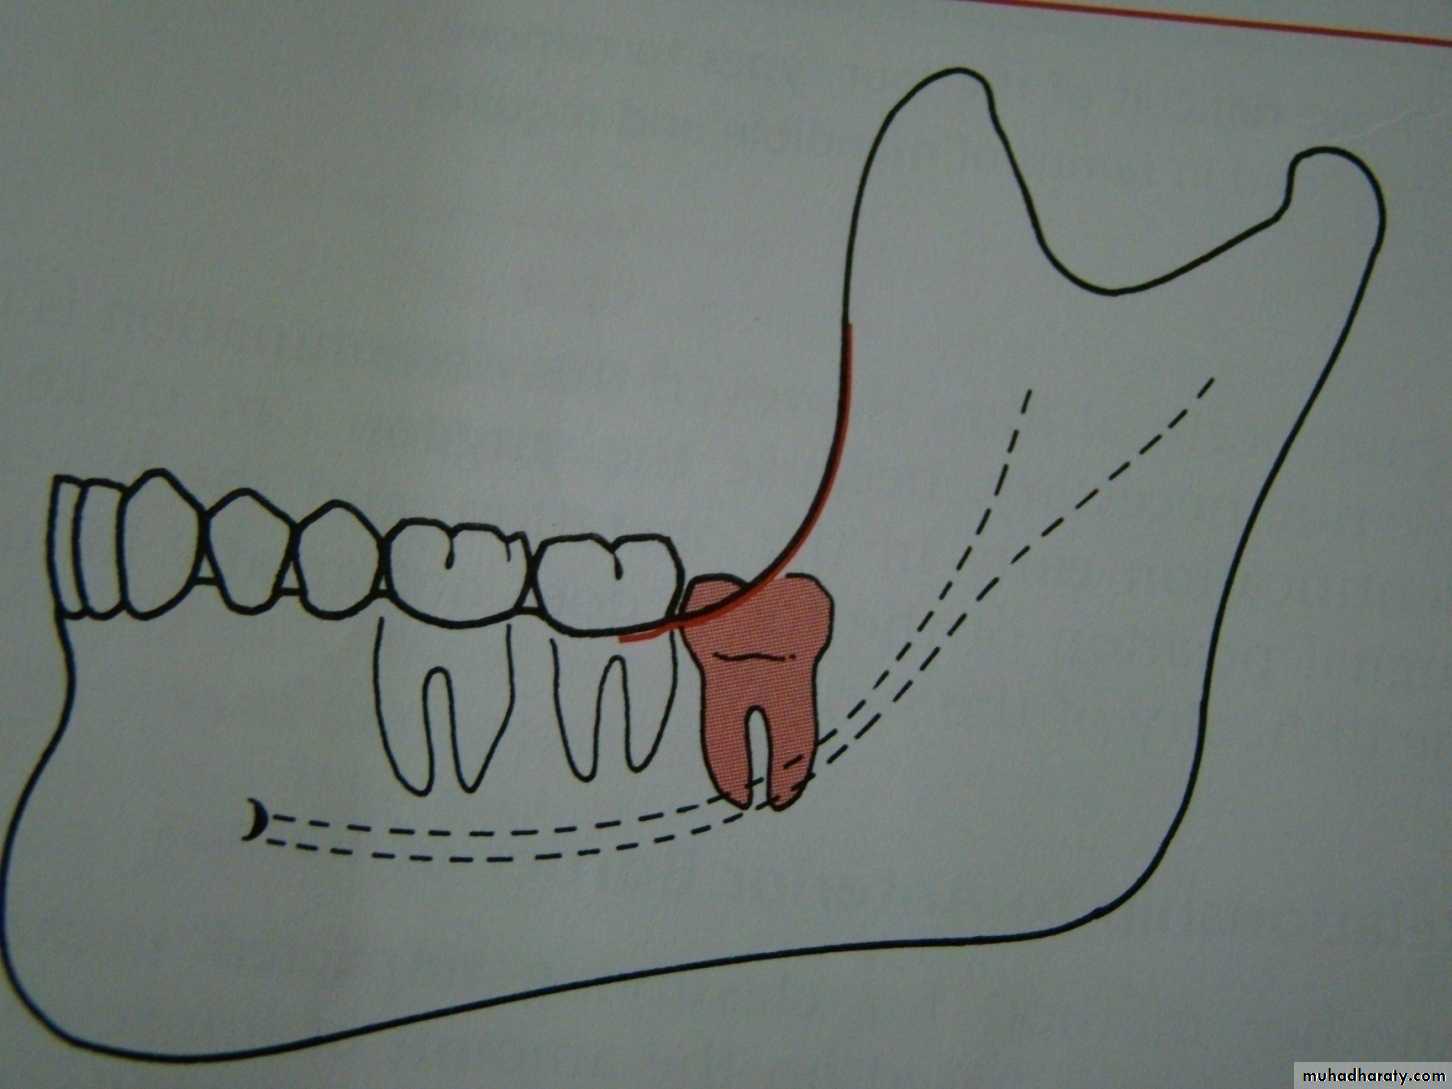

Winters classification of impacted lower third molar

mesioangular

hotizontalvertical

distoangular

Winter’s lines

1-White line: it is an imaginary line draw along the occlusal surface of erupted first and second molars extend posteriorly over 3rd molar region . Its benefit is to determine the angulations of an impacted tooth and its relationship with occlusal surface of erupted 2nd molar(depth).2- Amber line: It is a line drawn from the surface of bone laying distally to the 8 and to the crest of interdental septum or alveolar septum between 6 and 7. it determine the amount of bone removal

3-Red line : it is draw perpendicular from amber line to an imaginary point of elevator application located mesially to the CEJ except in Disto angular impaction it is distally located . It is used to measure the depth of the impacted tooth.

Note: Any tooth with red line length more than (5 mm) it is better to remove it under G.A.